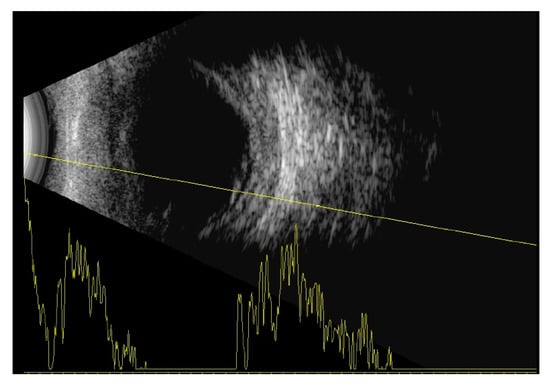

On admission, best corrected visual acuity (BCVA) was 10/200 in the right eye and 20/200 in the left eye. Ophthalmological examination of both eyes showed hyperemic conjunctival vessel, shallow anterior chamber, and detached retinas in the inferior periphery (almost to the vascular arcade on the right eye) (Figure 1).

Indirect ophthalmoscopy revealed yellowish exudates under the retina at the level of the choroid. Short axial length (right eye—14.35 mm, left eye—14.29 mm) and thickened choroid (2.68 mm—right eye, 2.56 mm—left eye) with inferior retinal detachments were diagnosed on the ocular ultrasound B-scan (Figure 2).

Figure 2. B-scan of the right eye with thickened choroid and inferior retinal detachment.